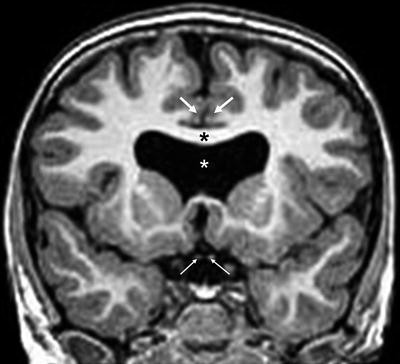

Septo-optic dysplasia. T2-weighted coronal MR image shows absent septum pellucidum (white asterisk denotes normal position) with characteristic squaring of the frontal horns of the lateral ventricles. Both optic nerves are hypoplastic (lower arrows). The corpus callosum (black asterisk) appears normal but there is mild holoprosencephaly with anomalous interdigitations of cerebral gray matter (upper arrows) just above the lateral ventricles.